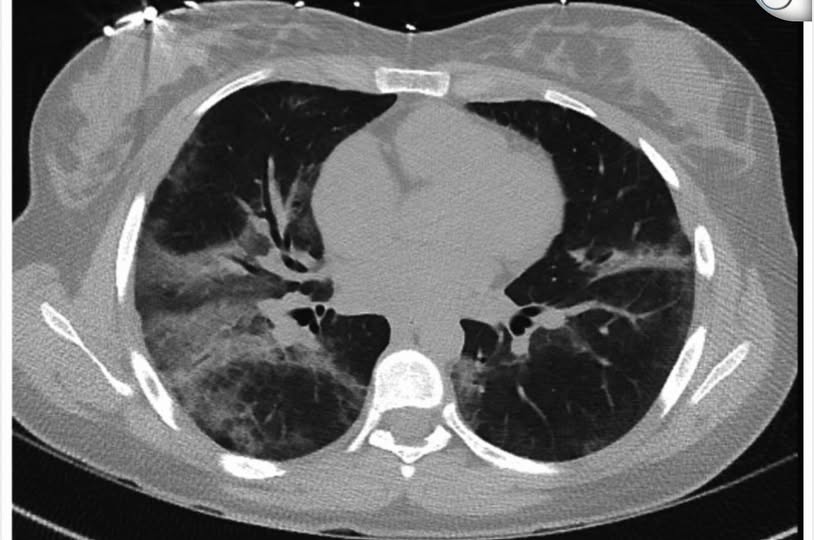

努鲁雅欣说,经过电脑断层扫描发现,少女的双肺呈“毛玻璃状阴影”(Ground Glass Opacities),这并非典型的肺炎,也不是癌症。

由于情况紧急,她遂为少女进行支气管镜检查及肺泡灌洗(BAL),检测结果显示肺泡中充满发炎细胞,包括中性球、淋巴球及巨噬细胞,因此确认是肺部炎症,而非细菌感染。

胸部X光显示小篓双肺再度布满阴影,白血球飙升至19.7,病情明显比上次更危急。